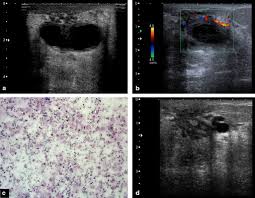

They can also occur in postmenopausal women taking hormone therapy. If the cyst comes back it may be evaluated again with mammogram and ultrasound and it can be drained again. On ultrasound a complex breast cyst will basically be treated in terms of internal echoes presence or absence of posterior enhancement thin septations and a thickened or irregular wall.

Breast cysts do not require treatment unless a cyst is large and painful or otherwise uncomfortable. On ultrasound a complex breast cyst will basically be treated in terms of internal echoes presence or absence of posterior enhancement thin septations and a thickened or irregular wall. A systematic review of the literature on sonographically detected complex breast cysts was carried. Management recommendations for complex cysts were 1-year follow-up in 13 patients 6-month follow-up in 148 sonographically guided aspiration in 82 aspiration with possible core biopsy in 62 and excisional biopsy in three. Your healthcare provider may want to perform a breast cyst aspiration or needle biopsy withdrawing fluid with a needle for analysis. Breast cysts dont require treatment unless a cyst is large and painful or uncomfortable. Not everyone is diagnosed with breast cysts and has treatment before pregnancy or childbirth. Complex breast cysts were estimated to be reported in approximately 5 of breast ultrasound examinations. Breast cysts can also be found in men although this is very rare.